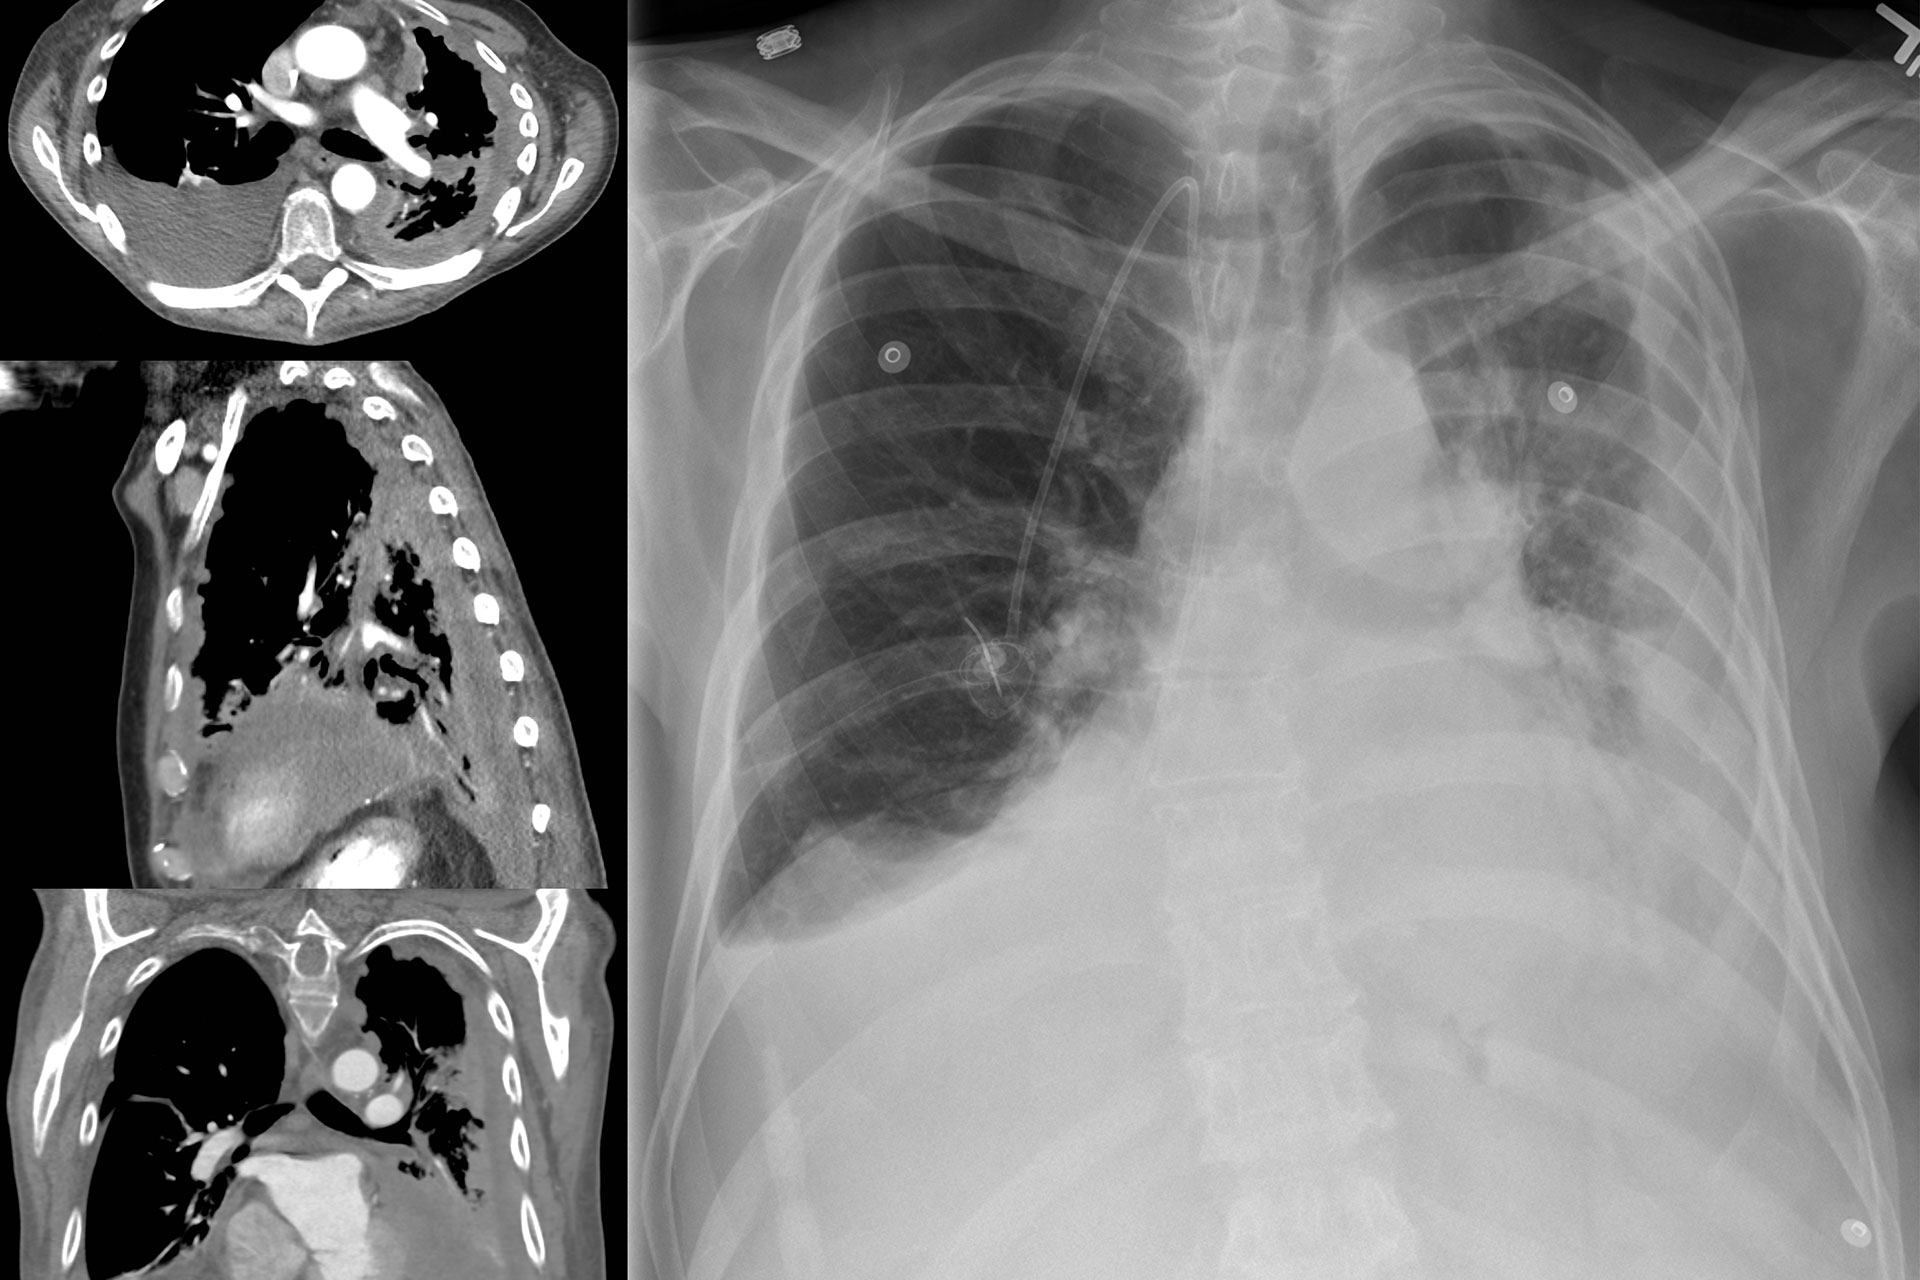

lung cancer asbestos

Lung Cancer

The inhalation of asbestos fibers poses a serious health risk, substantially increasing the chances of developing lung cancer. The fibers, often released into the air during the disturbance of asbestos-containing materials, can become lodged in lung tissue and lead to severe cellular damage over time.